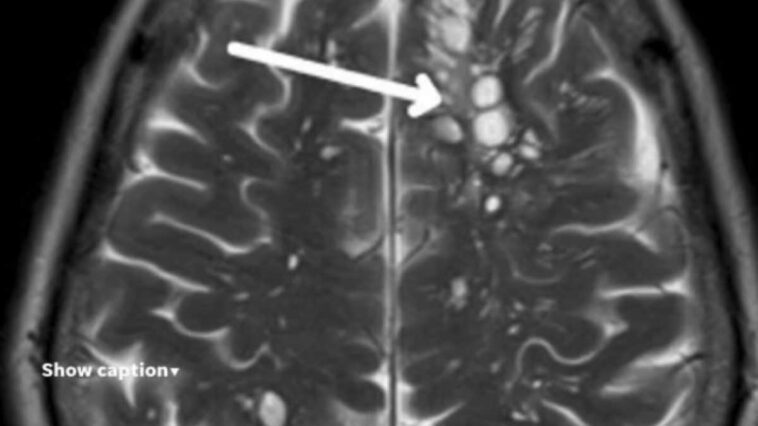

Un homme de 52 ans en Floride, aux États-Unis, est devenu un cas d’étude après avoir été diagnostiqué d’une infection parasitaire assez rare : la neurocysticercose. Il s’agit d’une maladie étroitement liée à la consommation de porc, causée par une infection par les larves du ténia du porc (Taenia solium) qui se forment en kystes dans le cerveau.

La téniose est une forme d’infection intestinale qui se produit lors de la consommation de viande de porc peu cuite contaminée par des œufs de ténia, tandis que la cysticercose est contractée lorsque des œufs présents dans les selles humaines de personnes ayant contracté la téniose sont ingérés. Cette dernière forme d’infection est presque toujours asymptomatique, à moins que les larves – appelées « cysticerques » – n’envahissent le système nerveux central, provoquant la neurocysticercose. C’est le cas du patient de 52 ans. Lorsque cette complication se produit, les personnes peuvent développer plusieurs symptômes tels que des maux de tête, parfois très intenses, des convulsions, de la confusion et d’autres symptômes neurologiques, qui peuvent être graves dans les cas extrêmes, comme l’explique le Manuel MSD.